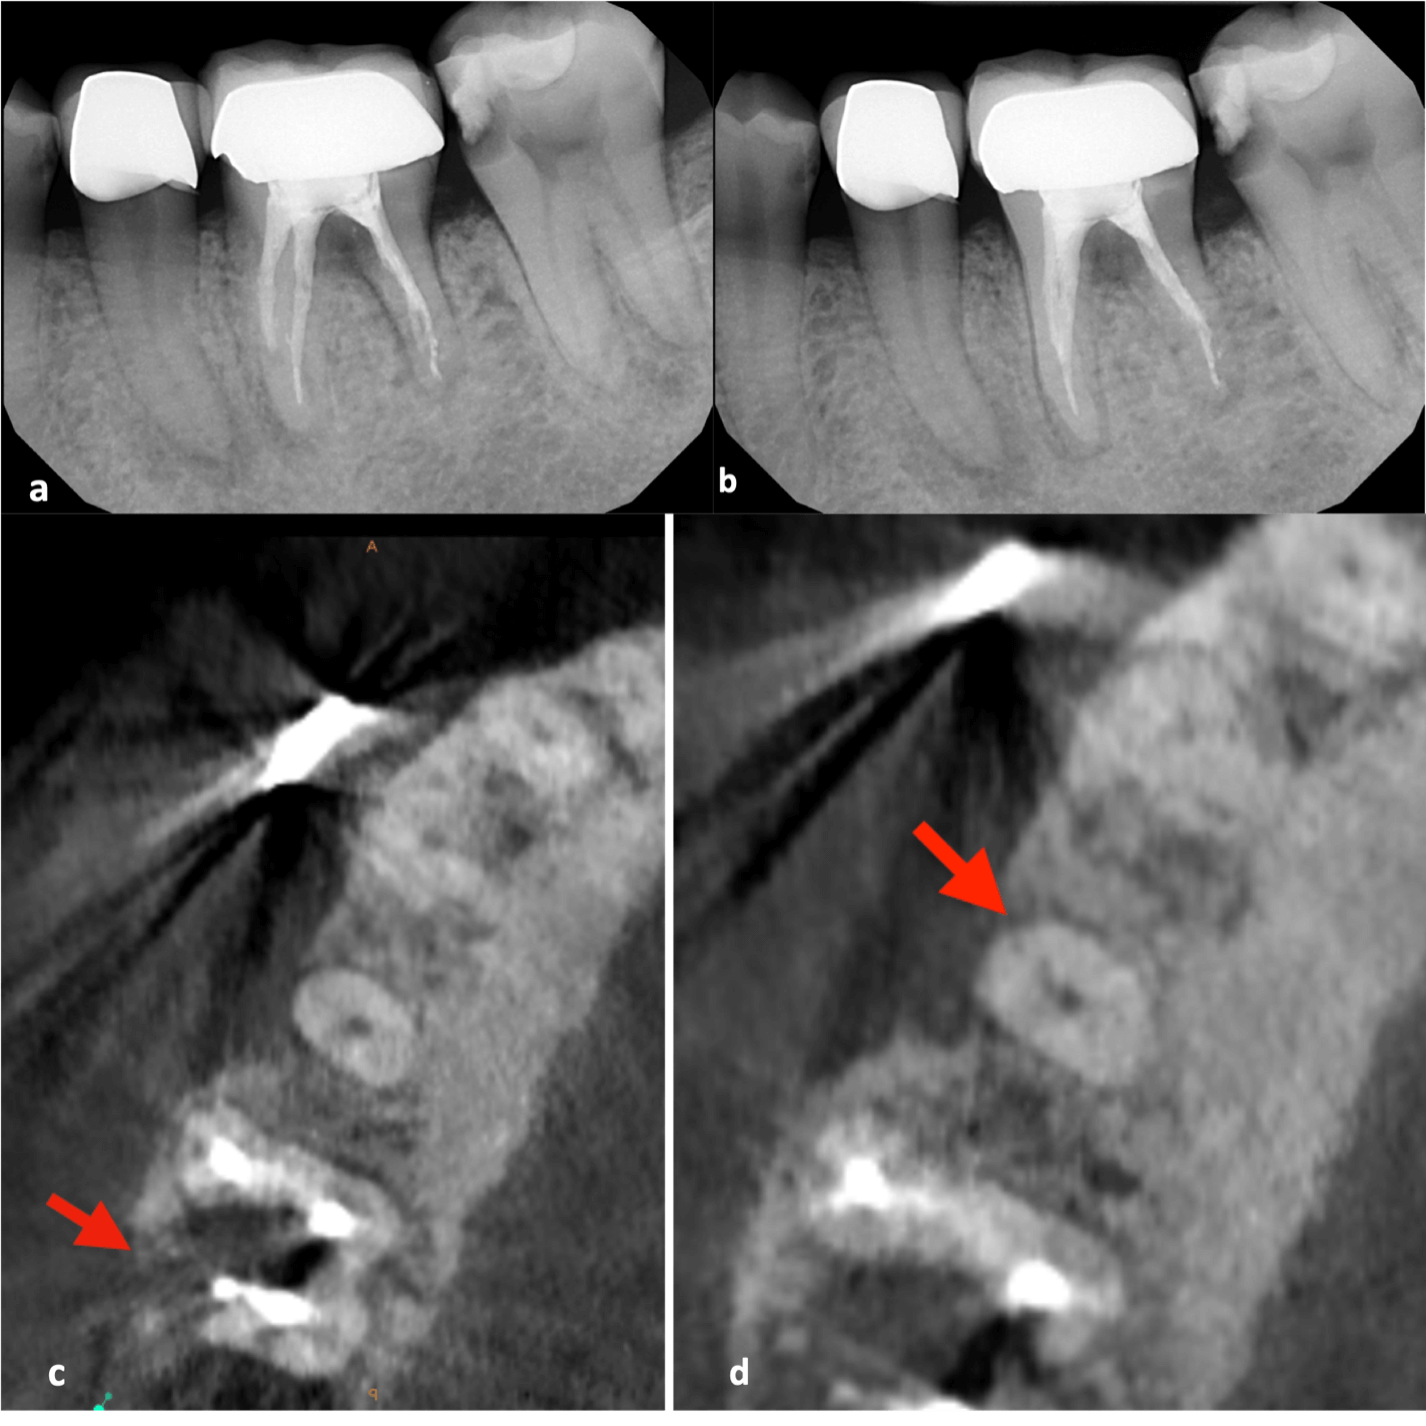

My first “wow” moment with CBCT was during the early years of the technology when scanning a patient after a traumatic dental injury that lead to lateral luxation of the maxillary left central incisor. The CBCT scan was able to produce images that previously had only ever been drawn or imagined. Those stunning 3D images have only gotten better over time. When indicated, 3D imaging provides critical information toward development of the best treatment plan. High-resolution images give endodontists the ability to change course and adapt quickly if needed to achieve better outcomes. Being able to diagnose a predictable failure also avoids unnecessary invasive procedures. For example, cases of root fractures or deep cracks (figure 1). For root canal retreatments understanding the etiology of the disease or failure is critical to obtain a positive outcome. CBCT also aids with enhanced visualization of traumatic injuries, particularly for crown, root fractures and luxation injuries (figure 2). Ultimately, the more accurate and realistic assessments of prognoses, the more predictable and positive outcome for my patients.

a-b. Periapical radiographs from different angles. Patient was referred for endodontic therapies on teeth 19 and 20 with apical lucencies consistent w